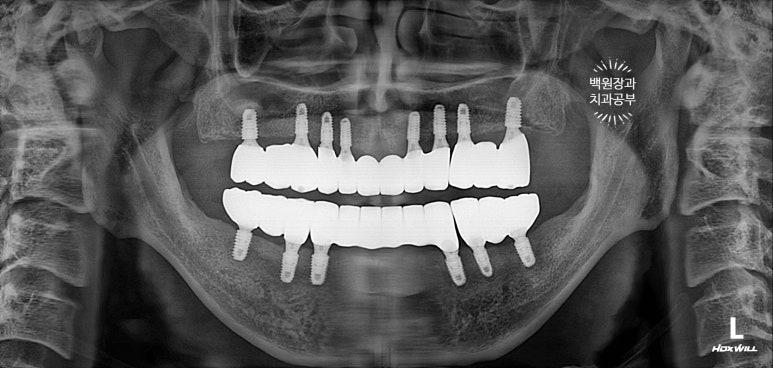

수술 후 촬영한 치과용 파노라마 사진에서 꽤나 예쁘게 심어진 임플란트를 확인할 수 있었습니다.

이렇게 위에는 8개의 임플란트가, 아래에는 6개의 임플란트가 예쁘게 식립된 것을 보실 수 있을겁니다.

깔끔하게 완성된 보철물은 치과용 파노라마 사진에서 확인하실 수 있고,

비전공자가 보아도 나란히 가지런한 임플란트는 편안함을 줍니다.

똑같아 보일 수 있으시겠지만, 6개월이 지난 후 치과용 파노라마 사진입니다.